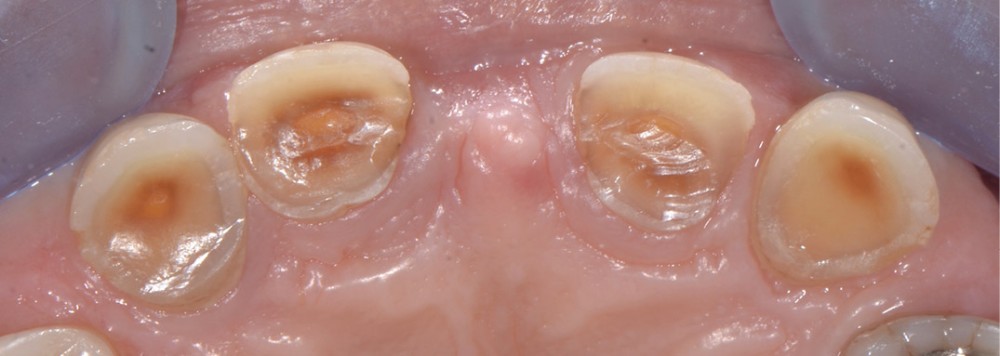

Prenons les lésions cervicales non carieuses, exemple typique de zone de dentine sclérotique (fig. 3) :

– la couche hyperminéralisée est épaisse dans la partie la plus profonde de la lésion. Elle présente deux espèces de bactéries : l’une piégée dans la partie minérale, l’autre se développant en tapis filamenteux à sa surface ;

– dans la partie occlusale de la lésion, la couche hyperminéralisée ainsi que la couche bactérienne de surface sont plus fines ;

– dans la partie gingivale de la lésion, la couche hyperminéralisée est encore plus fine (moins de 1 micron) et exempte de toute bactérie.